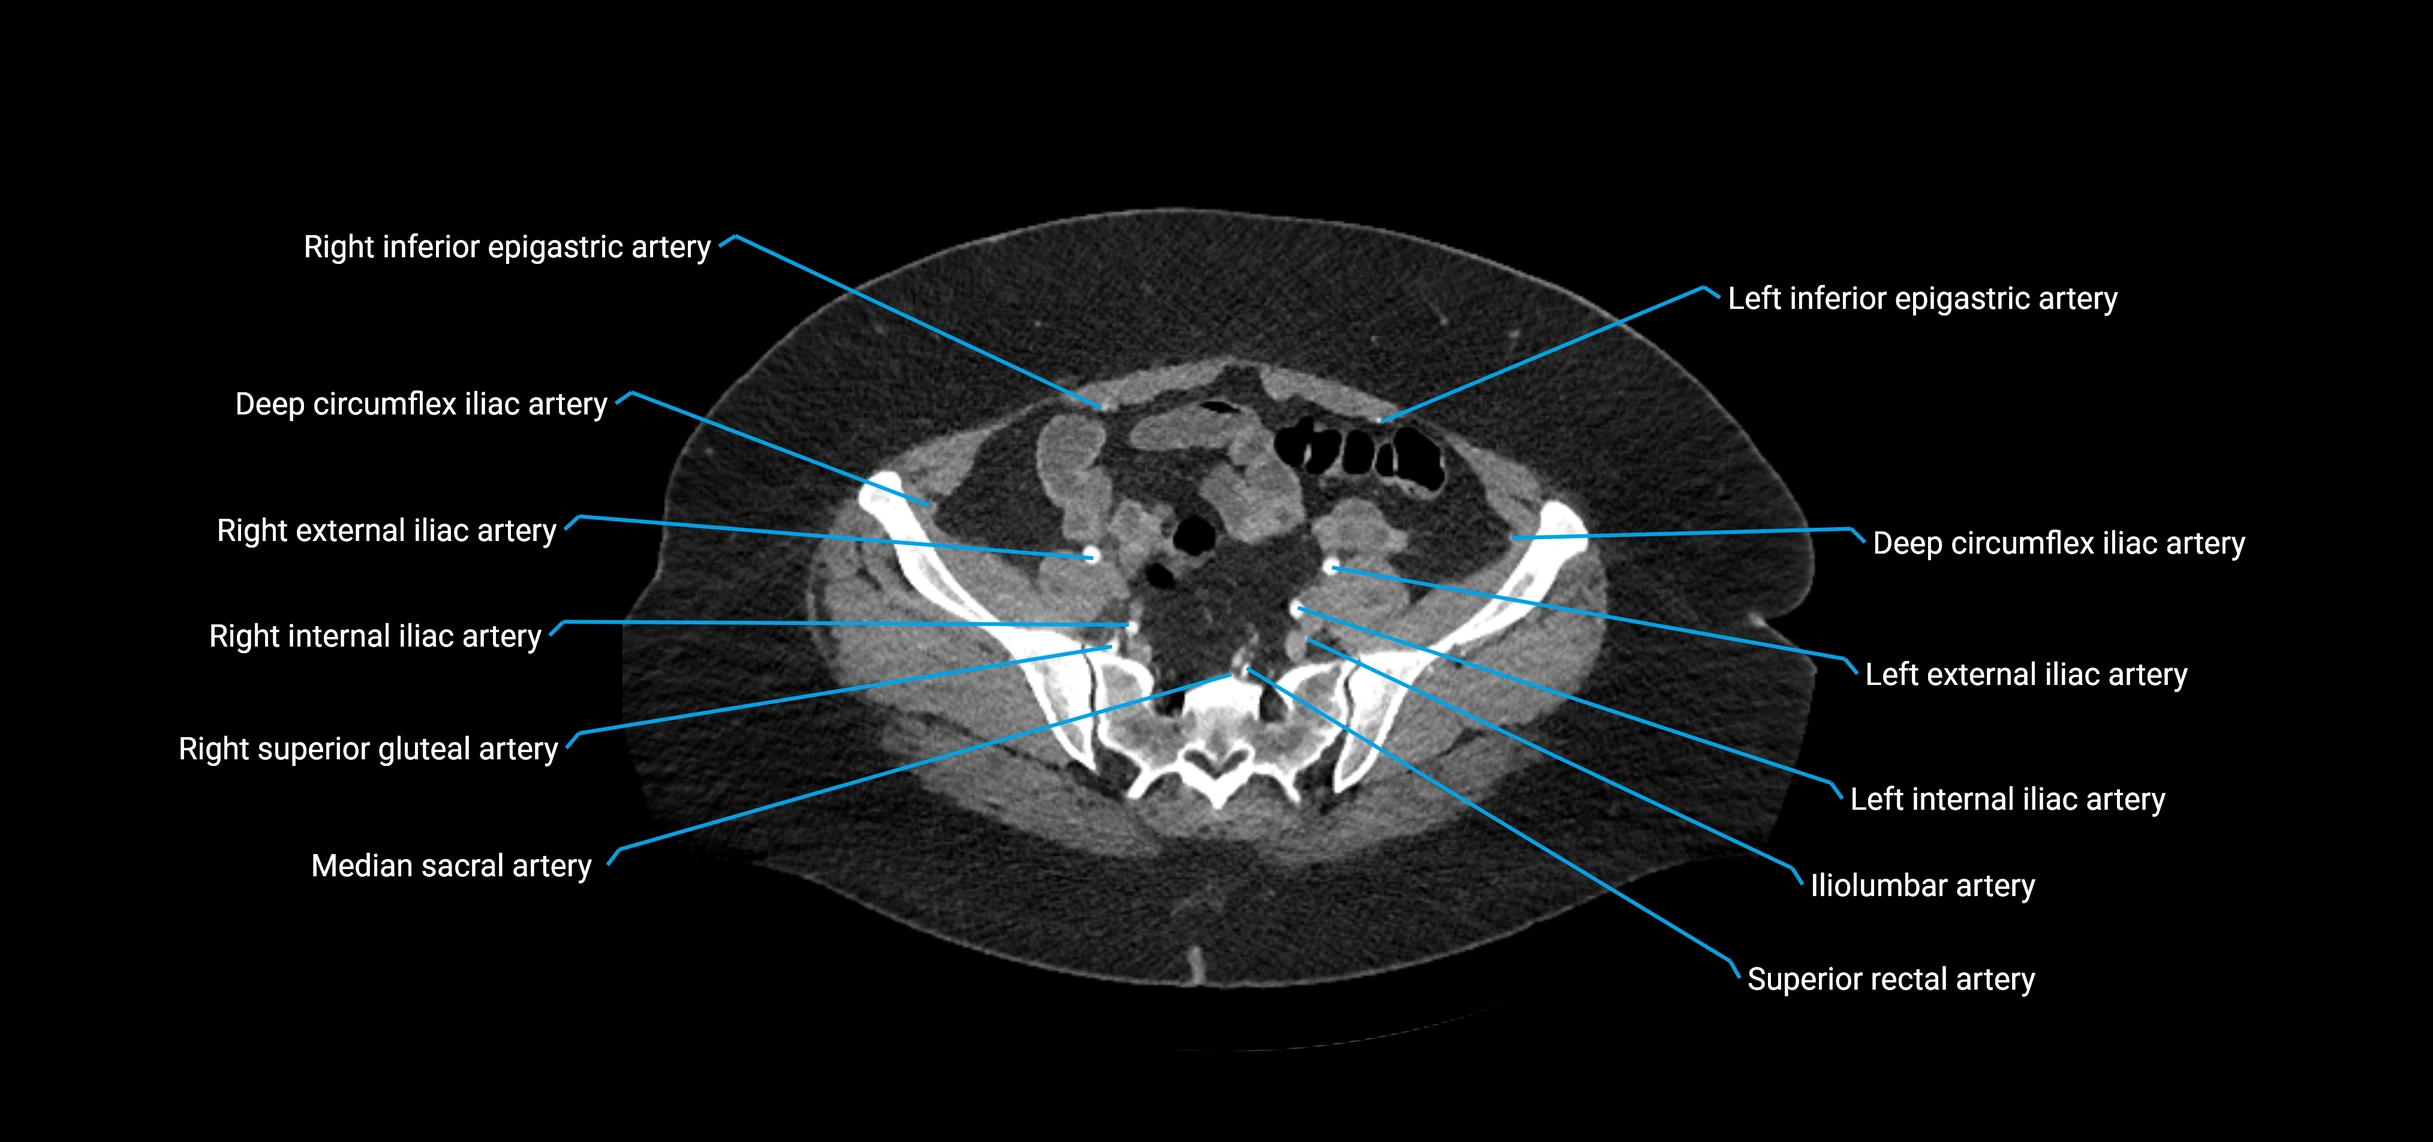

CT images

image

Contrast-enhanced CT (CTA):

• Gold standard for abdominal aortic imaging

• Provides excellent detail of lumen, wall, aneurysm, thrombus, and branch vessels

• Multiplanar and 3D reconstructions help in aneurysm measurement, stent graft planning, and dissection evaluation